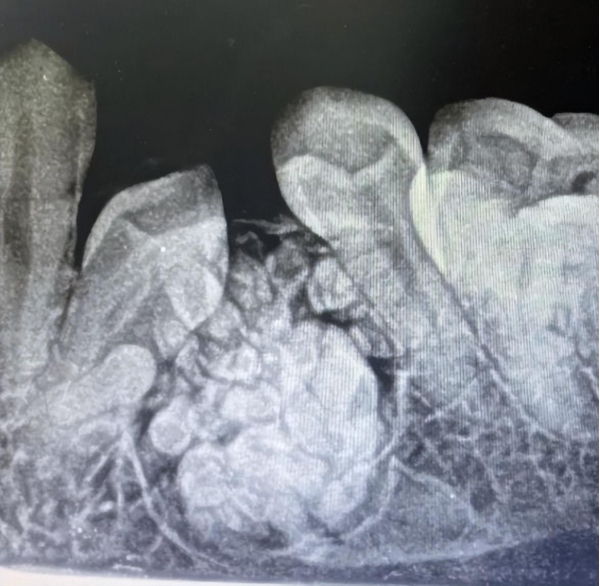

有网友发文表示,朋友从缺牙处拔出57颗牙,惊呆了一众网友。就连看牙的医生都兴奋的号召实习生们来围观。

有一天女孩突然去医院看了一下,结果医生说问题很严重,需要拍一个片子。拍片后医生一脸严肃的表示,要拍一个更详细的片子。这时,医生把他的实习生全部都叫了过来,女孩意识到事情不太对劲了。